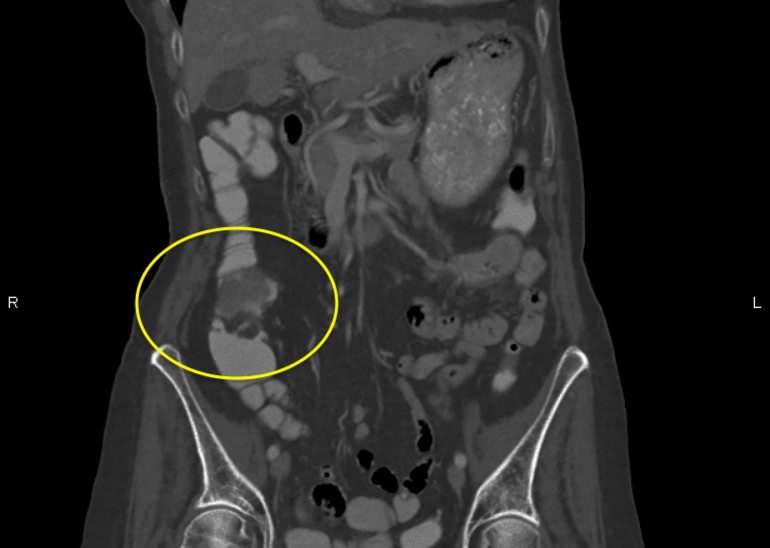

Results of a transthoracic echocardiogram (TTE) were negative for endocarditis, and a computed tomography (CT) scan of the abdomen and pelvis with intravenous contrast showed a 3 × 2-cm soft-tissue mass located at the proximal ascending colon (Figure 1).

Figure 1. Coronal view of abdominal and pelvic CT showing a 3 × 2-cm mass.